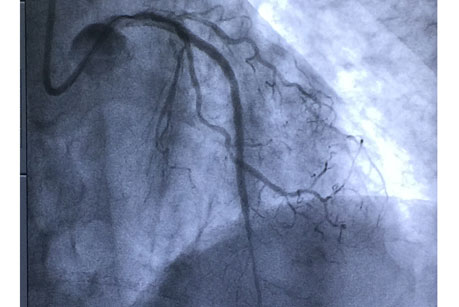

手术在11月6日进行,由赵慧强主任、张文广副主任医师担任术者。手术穿刺了两侧的桡动脉,均置入指引导管,微导管支持下送入前向导丝拟开通CTO病变,但闭塞病变处严重钙化,经尝试不能通过闭塞段到达远端真腔。鉴于右冠向左前降支发出良好的侧枝循环,此时果断地采用逆向导丝技术,首先干预右冠近端及远端病变,搬开逆向导丝应用的“绊脚石”,在微导管支持下专用导丝依次通过右冠后降支→侧枝循环→间隔支→前降支闭塞病变远端,逆行进入前降支闭塞病变远端,但逆向微导管未能送入侧枝内,遂改变策略再反复调整前向导丝前进,最终前向导丝与逆向导丝“抱紧”,成功通过闭塞病变到达前降支远端病变真腔,顺利完成支架置入。术后患者未再发作胸憋、胸痛,已顺利出院。

此次,心内科采用内逆向导丝技术成功完成CTO病变,不仅为我院及平谷区首例,也标志着我院的冠脉介入技术达到了市内先进水平。今后,我院心内科介入团队将继续努力不断提高技术水平,更好地为平谷区人民服务,使平谷区人民在本地就能享受到高水平的医疗。